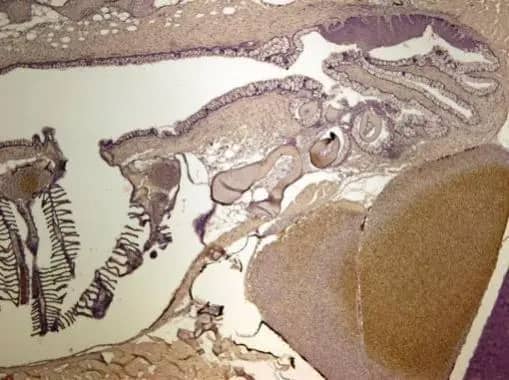

Immunohistochemistry-Paraffin: Calcineurin B Antibody [NBP1-32720]

Immunohistochemistry-Paraffin: Calcineurin B Antibody [NBP1-32720] - Paraffin-embedded NCI-N87 xenograft, using antibody at 1:500 dilution.